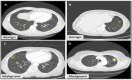

Recently, deep learning and the Internet of Things (IoT) have been widely used in the healthcare monitoring system for decision making. Disease prediction is one of the emerging applications in current practices. In the method described in this paper, lung cancer prediction is implemented using deep learning and IoT, which is a challenging task in computer-aided diagnosis (CAD). Because lung cancer is a dangerous medical disease that must be identified at a higher detection rate, disease-related information is obtained from IoT medical devices and transmitted to the server. The medical data are then processed and classified into two categories, benign and malignant, using a multi-layer CNN (ML-CNN) model. In addition, a particle swarm optimization method is used to improve the learning ability (loss and accuracy). This step uses medical data (CT scan and sensor information) based on the Internet of Medical Things (IoMT). For this purpose, sensor information and image information from IoMT devices and sensors are gathered, and then classification actions are taken. The performance of the proposed technique is compared with well-known existing methods, such as the Support Vector Machine (SVM), probabilistic neural network (PNN), and conventional CNN, in terms of accuracy, precision, sensitivity, specificity, F-score, and computation time. For this purpose, two lung datasets were tested to evaluate the performance: Lung Image Database Consortium (LIDC) and Linear Imaging and Self-Scanning Sensor (LISS) datasets. Compared to alternative methods, the trial outcomes showed that the suggested technique has the potential to help the radiologist make an accurate and efficient early lung cancer diagnosis. The performance of the proposed ML-CNN was analyzed using Python, where the accuracy (2.5-10.5%) was high when compared to the number of instances, precision (2.3-9.5%) was high when compared to the number of instances, sensitivity (2.4-12.5%) was high when compared to several instances, the F-score (2-30%) was high when compared to the number of cases, the error rate (0.7-11.5%) was low compared to the number of cases, and the computation time (170 ms to 400 ms) was low compared to how many cases were computed for the proposed work, including previous known methods. The proposed ML-CNN architecture shows that this technique outperforms previous works.

Figures